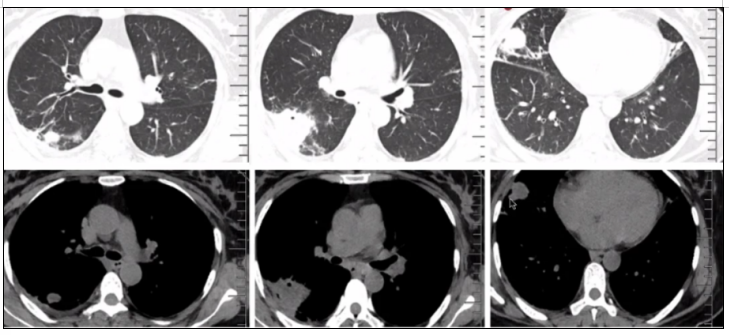

TSM的影像学表现多种多样。

病例1:患者53岁,主诉反复咳嗽、发作性喘息5月余,加重伴发热5 d。临床表现没有特异性,肺部影像学可见多发结节,有些结节靠近胸膜下,但无明显晕征,有大片实变影,其中可见支气管气象。纵隔窗可见结节及实变影,并未出现明显增强10

图片

图10  TSM患者肺部影像学表现

相关文献也提示,TSM的影像学既可以表现为肺内多发结节,也可以有多发空腔样改变,还可以伴有双侧胸腔积液,甚至引起播散性感染,导致腹腔淋巴结肿大,脾大,脾内多发低密度病灶(图17)。有时PET-CT直接回报肺癌、癌性淋巴管炎、纵隔淋巴结转移,或直接回报疑似淋巴瘤。

图17  TSM患者影像学表现

从上述病例的影像学可以看到,TSM的影像学表现多种多样,包括大片实变、结节、磨玻璃改变、粟粒样病变、肺门或纵隔淋巴结肿大、胸腔积液、空洞、坏死,以及细菌性肺脓肿,内壁光滑,甚至有气液平面,这与我们既往所认识的真菌影像学特征有所不同。研究显示,大部分HIV阳性患者胸部影像学表现形式多样,45.6%表现为斑片状浸润影或局限性肺实变,较少形成空洞病灶(8.0%)。HIV阴性TSM患者胸部影像学表现与HIV阳性患者相似,主要表现为肺部浸润影伴或不伴间质性改变,亦常出现胸腔积液。